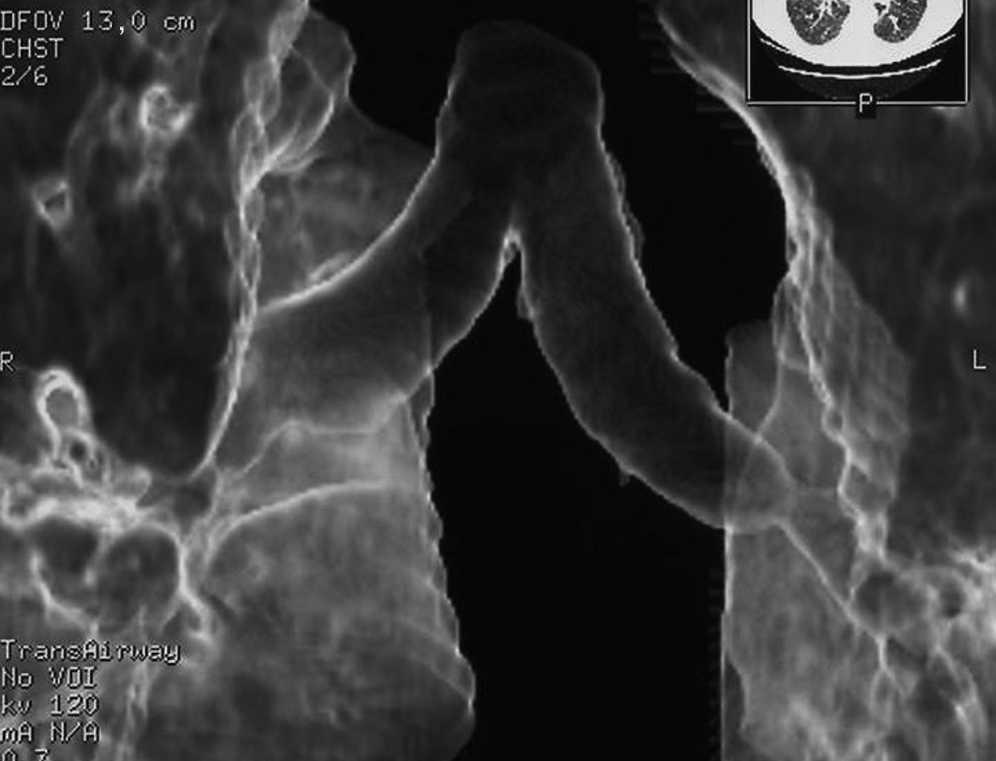

Multisection CT with 2D and 3D reconstructions is very useful to diagnose such bronchial complications. Furthermore, it allows measurements to be obtained for stent implant and a later follow-up not requiring bronchoscopies which are more invasive and bothersome for patients. Sixty-four sections are used, with a fast image acquisition and radiation dose modulation.

Figure 2. Multisection CT with 3D reconstruction showing a stenosis distal to right bronchial suture in double-lung transplantation.